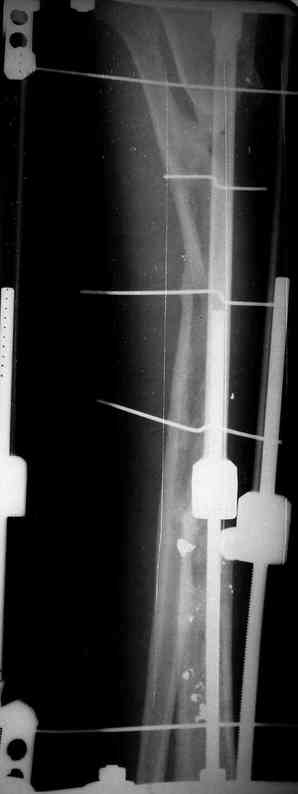

Реализовал описанную выше методику, и в итоге вот что получилось. Высылаю лишь прямые проекции,

в боковых тоже всё в тему.

Очень пригодились карбоновые кольца (Джолдас -огромное спасибо, я твой должник!!!), поскольку остеопороз дистального отломка был просто невероятный. На цифровом рентгене с трудом угадывались контуры.

Рентген в процессе перемещения - внизу карбоновые кольца, тракция фрагмента спицами с упором.

внешний вид в аппарате - не завершающем этапе, сначала стопа тоже была фиксирована в аппарате.